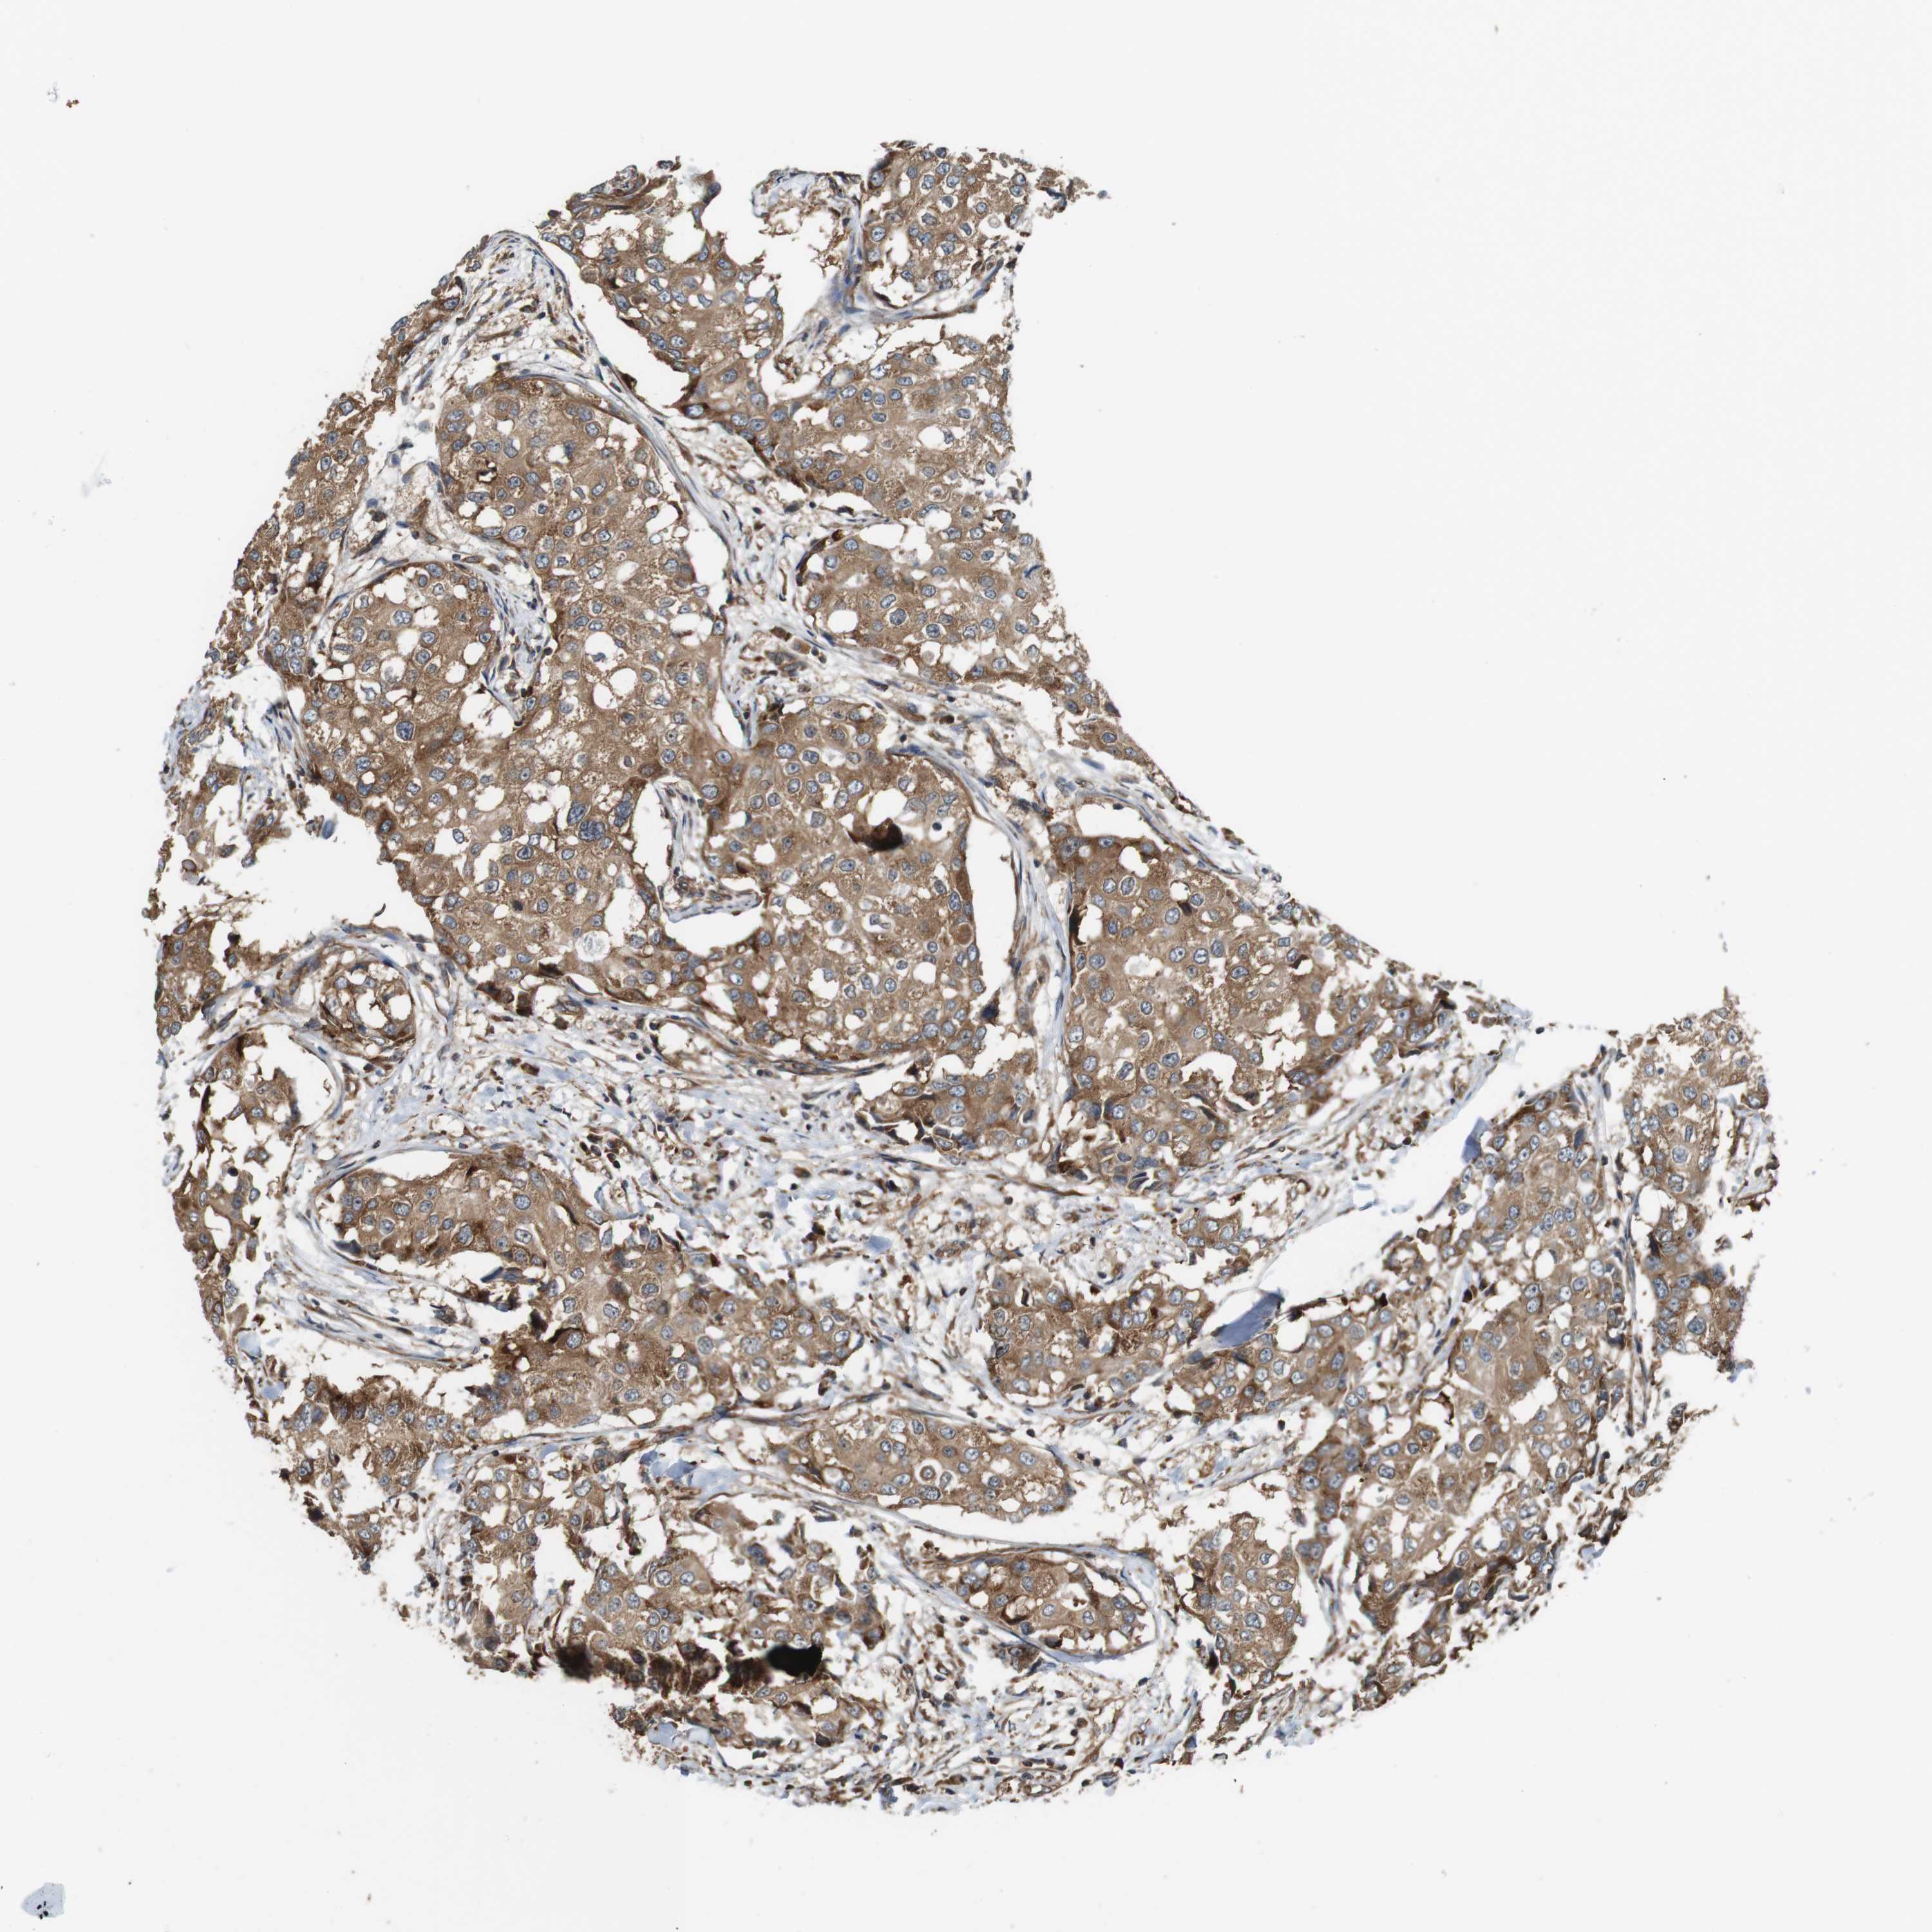

BRCA TCGA BRCA VALIDATION PROTEIN EXPRESSION

Breast cancer

Human cancer